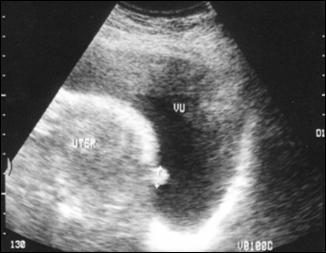

c) Sterilet migrat intravezical, complicat cu hematurie

a. b.

c.

a) Ecografie vezicala, evidentiind steriletul migrat intravezical; b) RRVS la aceiasi pacienta; c) Steriletul dupa extractie prin cistoscopie.